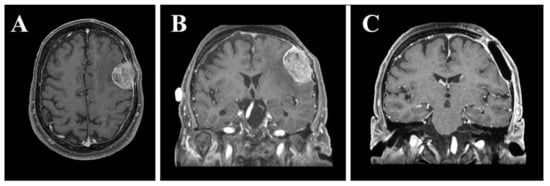

In this laboratory-based study, we retrospectively used the preoperative and post-operative magnetic resonance imaging (MRI) sequences (Figure 1) of a 68-year-old right-handed male with en plaque meningothelial meningioma (Grade I according to WHO classification) [27], with diffuse and extensive dural involvement, extracranial extension into the calvarium and homogeneous contrast enhancement on gadolinium-enhanced T1-weighted MRI, who underwent surgery at our University Hospital. Meningothelial cells invaded and expanded the left fronto-temporal bones promoting local bone thickening, and in addition, extensive hyperostosis was associated with infiltration of the subarachnoid space, configuring itself as en plaque meningothelial meningioma. For this reason, after tumor resection, the bone flap obtained during craniotomy was not placed and cranioplasty with polymethylmethacrylate (PMMA) cement was performed (Figure 1C). The following paragraphs briefly describe the materials and methods for simulating the craniotomy guided by the VOSTARS system, in a manikin’s head that replicated the anatomy of the above-mentioned surgical case.

Figure 1.

Preoperative axial (A) and coronal (B) gadolinium-enhanced T1-weighted MRI showing en plaque convexity meningioma. Postoperative coronal gadolinium-enhanced T1-weighted MRI (C) showing surgical resection of the tumor and cranioplasty with polymethylmethacrylate.